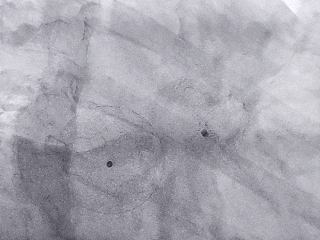

封堵器展开后造影

封堵器完全展开,封堵器未露肩

封堵器稳定封堵,无残余分流

封堵器释放后造影评估

Lefort封堵器评估符合PASS原则,释放封堵器,封堵器位置稳定且未见残余漏